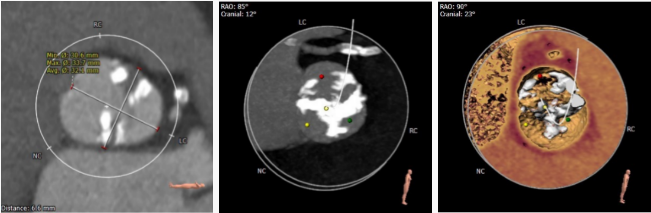

瓣叶分型

根据瓣环的截面分析,

二叶瓣Type1,极重度钙化,可见右无有钙化脊

可根据术中球囊扩张决定

是否Down size

球囊选择

根据瓣环平面/钙化程度、瓣叶分型可以初步选择26/23球囊

8*40球囊预扩,20球囊再次预扩可以进一步确认支架型号

钙化评估

1.钙化极重度,右无冠窦存在钙化脊,支架会偏向左冠窦

2.二叶瓣容易发生瓣膜移位,此病例可以尝试进行高位释放